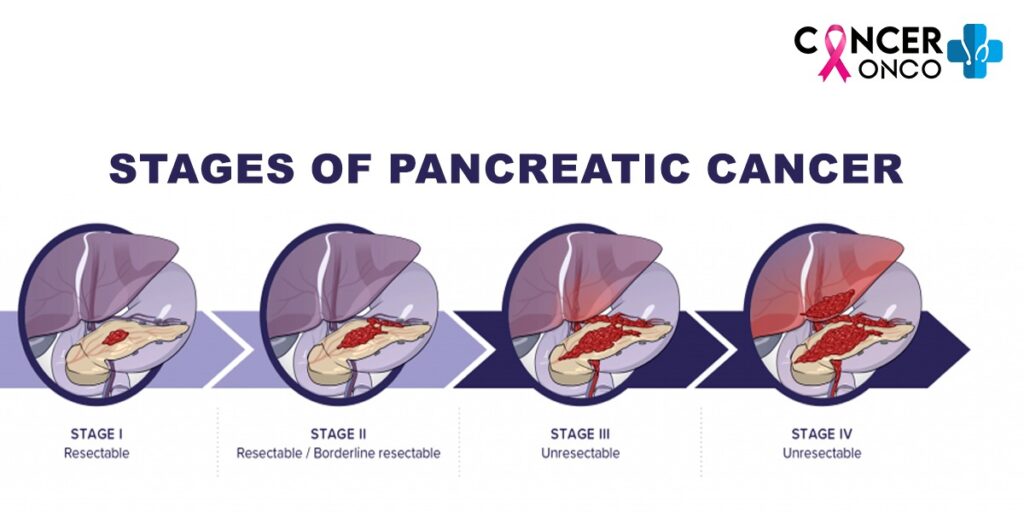

Pancreatic Cancer Treatment 2024 Kimmi Charmine

Pancreatic Cancer After Whipple Surgery - [desc-14]